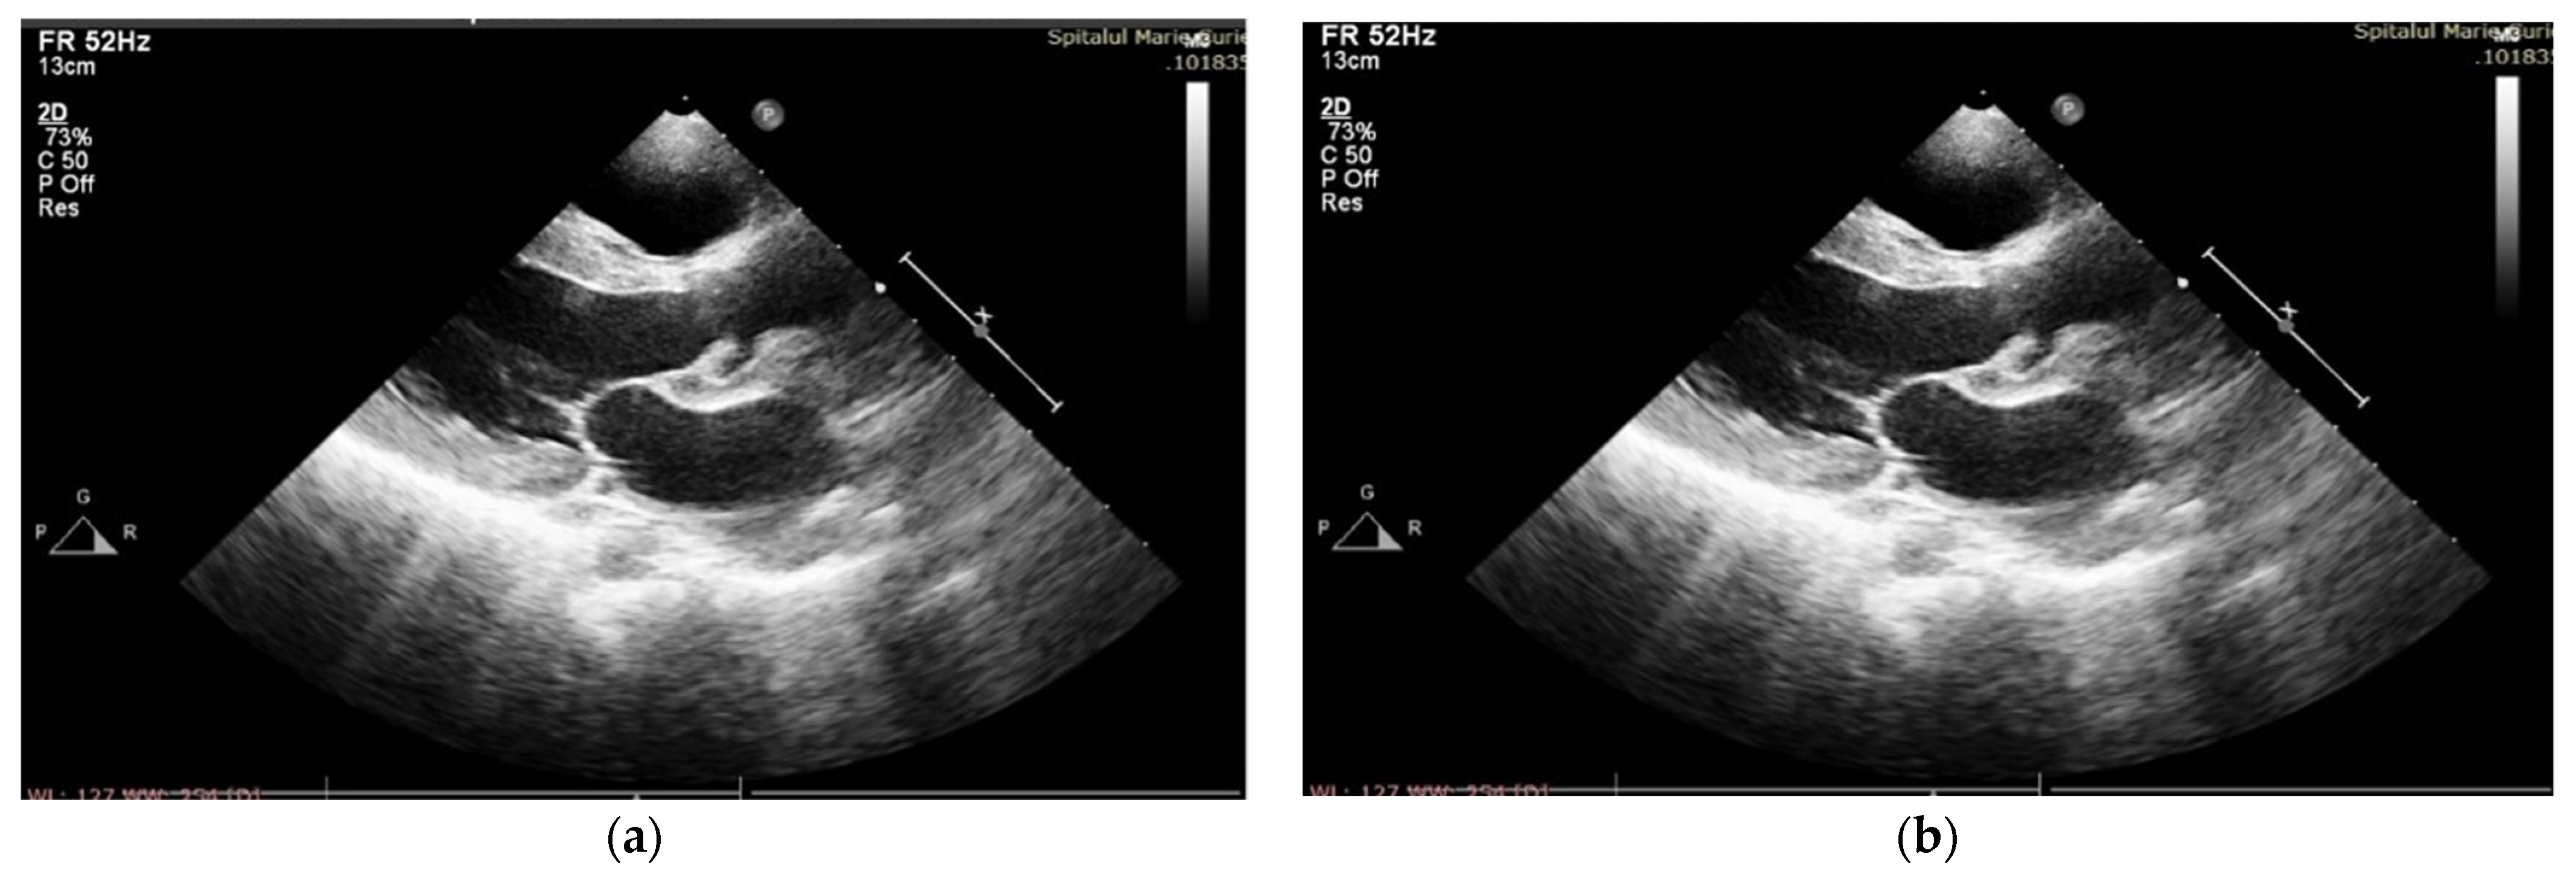

After four days of admission, vesper fever (38.2 C) progressively recurred, and the biological inflammatory syndrome slowly developed. Management was changed to Meropenem at 100 mg/kg/day and Linezolid at 25 mg/kg/day (Vancomycin was replaced with Linezolid due to a severe allergic reaction after the second administration), and this was continued for six weeks. In the first week of treatment, the patient started to develop a significant new diastolic murmur, and echocardiography confirmed spontaneous drainage of the perivalvular aortic abscess, resulting in severe aortic insufficiency and dilation of the left aortic coronary sinus (Figure 1a,b), along with a decrease in LVEF (45%).

Figure 1. (a) TTE PLAX—paravalvular aortic abscess—in the course of formation; (b) after spontaneous evacuation.